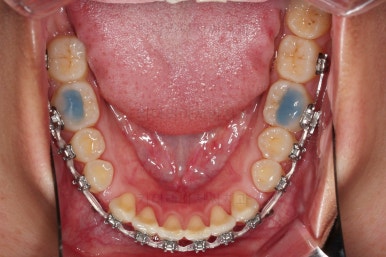

아랫니 틈은 거의 없어졌네요.

대신 여러 교합적인 이유로 아랫니를 좀 더 앞으로 당겨주긴 해야 합니다.

이제 마무리를 해봅니다.

교합 양호하고 치아 사이 틈새도 잘 모아졌습니다.

특히나 틈새가 있었던 환자분의 교정치료는 재발을 할 우려가 크므로 원인 요소가 되는 부분들을 잘 찾고 개선해주며 유지장치도 좀 더 광범위하게 부착해 줍니다.